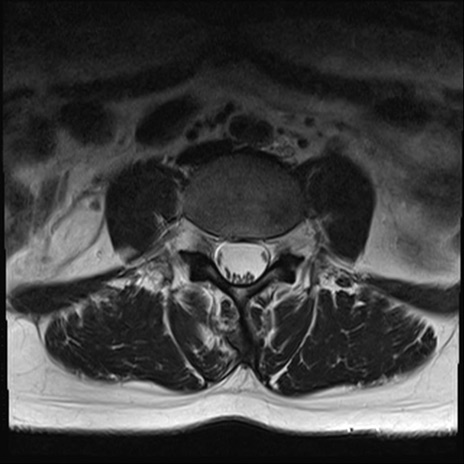

【整形】TIPS症例4 腰椎MRI T2WI(横断像)

腰椎MRI

横断像と矢状断像